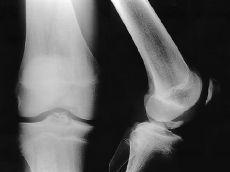

Figura 2. Niño de 15 años de edad con fractura avulsión del LCP y fractura asociada de la diáfisis del fémur. A: Radiografía preoperatoria. B: Radiografía a los 6 meses de evolución.